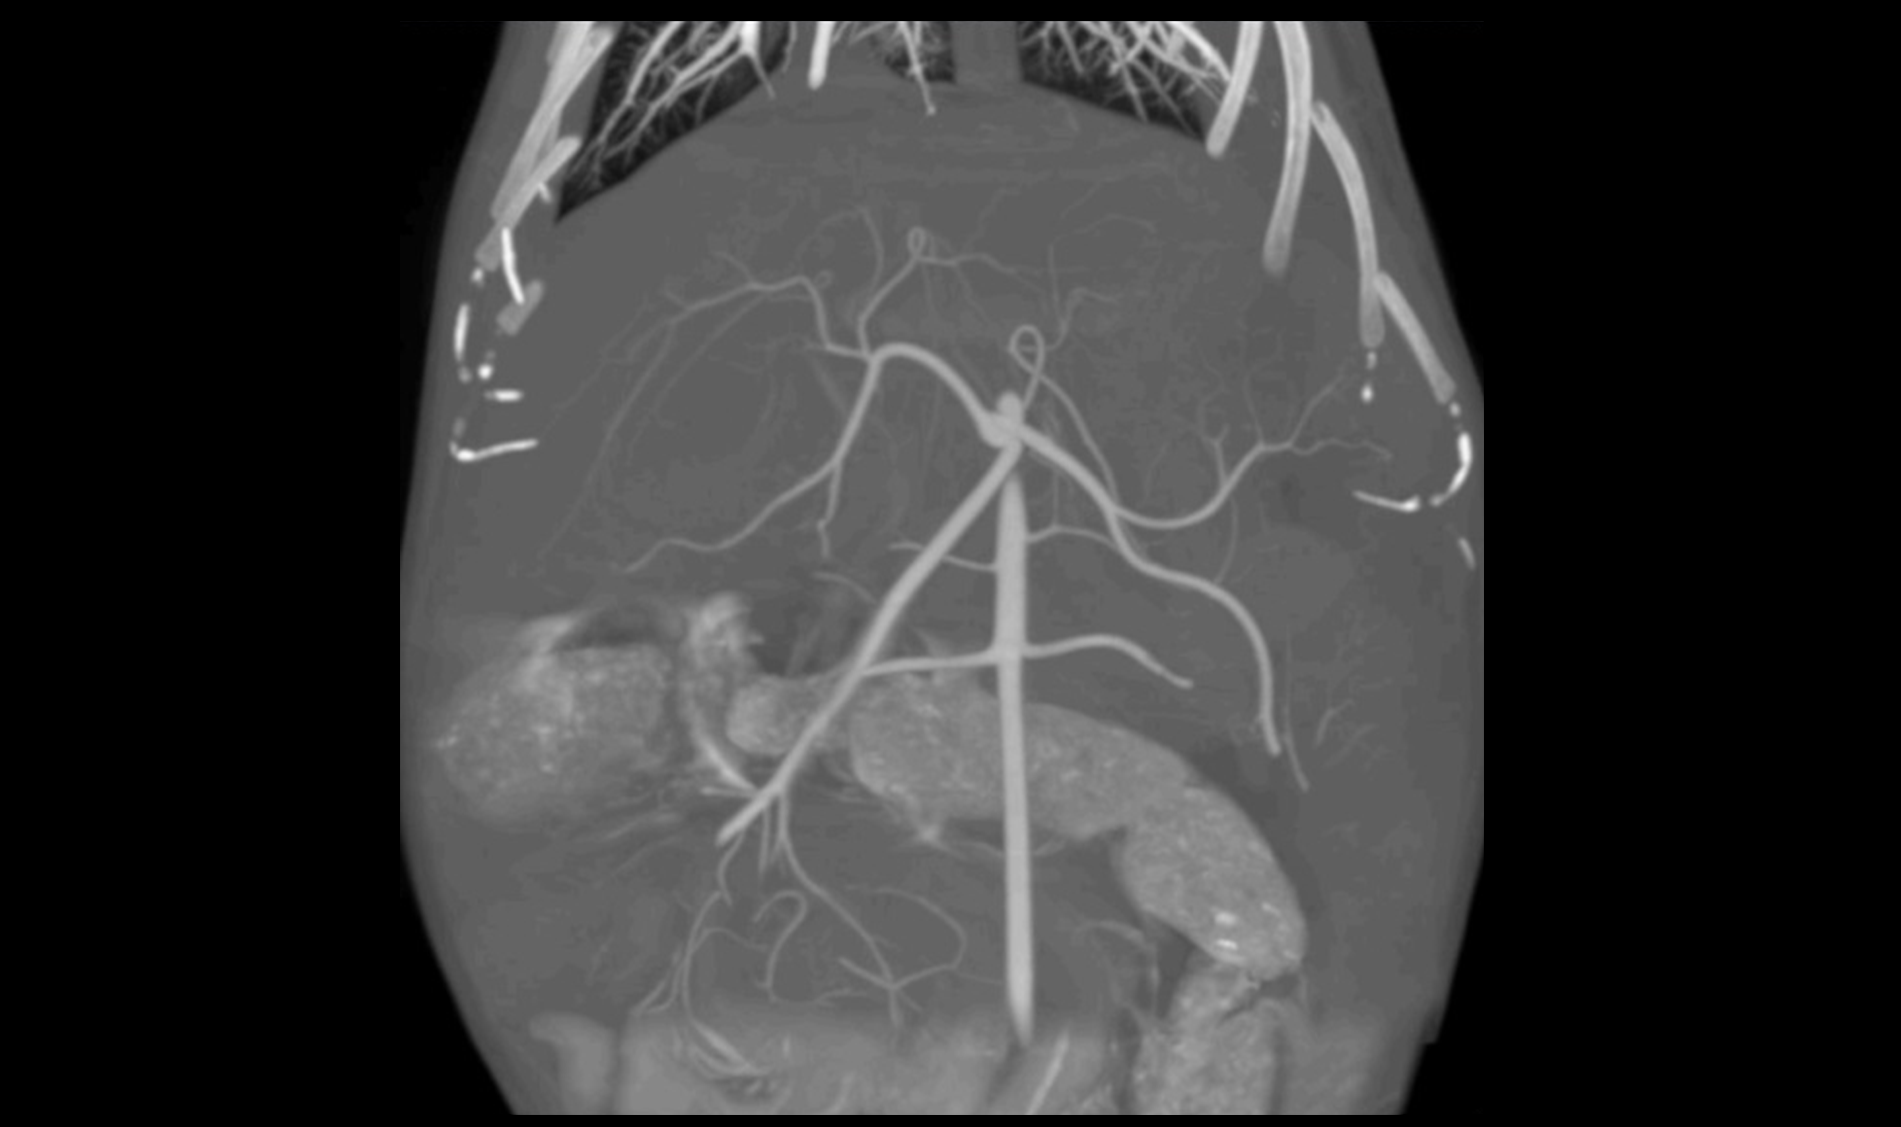

HDVI and HRCT

NON INTERPOLATED 3D DATA VOLUME REPRESENTATION

Acquisition of volumes with 100% real data: perfect for augmented reality, orthopedics and image-guided procedures.

Dr Scott Echols

"We really don't know that much about the anatomy of a lot of these animals. However, we have never had a way to visualize it like we can now and each scan that we perform is a whole new treasure trove of data. We can literally see each blood vessel in the body."

DVM, DABVP,

Parrish Creek Veterinary Hospital & Diagnostic Center